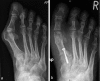

Figure 4

Radiographs of a foot with mild hallux valgus

Figure 5

Radiographs of a foot with severe hallux valgus